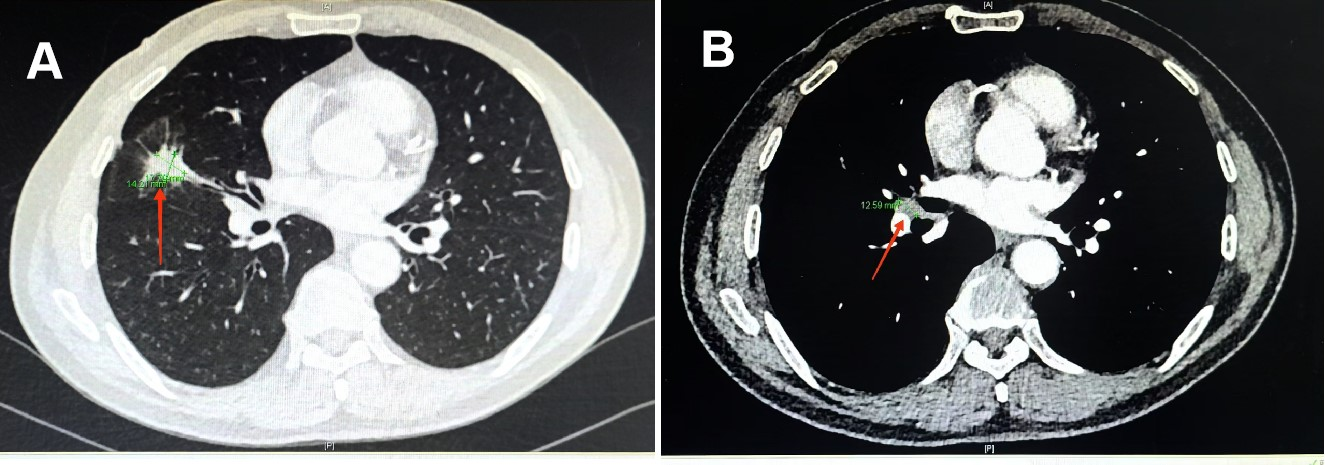

经过4个周期的治疗,向先生的肺部病灶显著缩小,肺门淋巴结也明显缩小(见图3),整个治疗过程中也没有发生明显的不良反应。经过医院MDT(多学科团队协作)会诊,向先生的小细胞肺癌分期成功由IIIA期降至IIA期,大家一致认为已达到手术条件和要求。8月23日新桥医院胸外科在全麻下为向先生做了肺癌根治性切除手术。手术过程顺利,术后的病理结果显示切除的病灶和淋巴结中没有发现肺癌细胞,达到了病理完全缓解(PCR)(见图4)。向先生术后恢复良好,精神状态和气色俱佳,5天后高兴地出院回家。

图3 经过4周期治疗后肺部原发病灶明显缩小(见图A红色箭头)和肺门淋巴结明显缩小(见图B红色箭头)